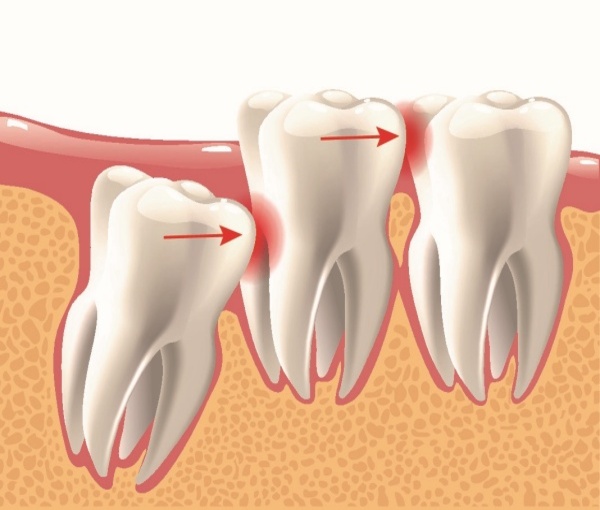

- Cung hàm không đủ chỗ: Đây là nguyên nhân phổ biến nhất. Khi răng số 8 bắt đầu mọc, toàn bộ các răng khác trên cung hàm đã ổn định vị trí. Nếu xương hàm của bạn có kích thước nhỏ hoặc các răng khác quá lớn, không còn đủ khoảng trống, răng khôn buộc phải tìm đường mọc theo hướng bất thường, dẫn đến mọc nghiêng, mọc lệch hoặc mọc kẹt, mọc ngầm hoàn toàn dưới nướu và xương hàm.

- Sự cản trở từ răng số 7: Răng 8 mọc ngầm thường gặp sự cản trở từ chân hoặc thân răng số 7 ở phía trước, khiến nó không thể trồi lên đúng vị trí thẳng đứng.

Viêm lợi trùm: Nướu phủ lên răng khôn khiến thức ăn, vi khuẩn mắc kẹt, gây sưng đau, viêm nhiễm, khó nhai nuốt.

Sâu răng và viêm nha chu: Răng 8 khó vệ sinh dễ sâu răng, lây sang răng 7 và gây viêm nha chu cho vùng hàm.